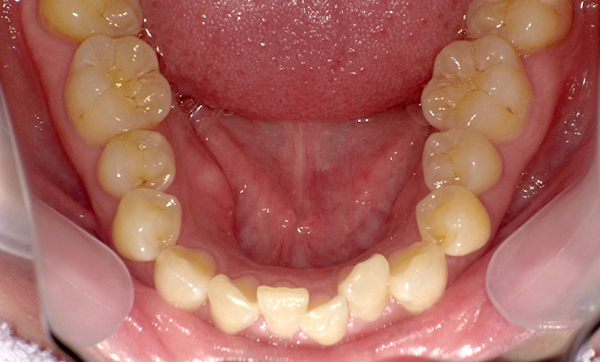

症例_009 「上下の前歯」症例

治療期間:7ヶ月金額:54万円+税20代女性捻転歯一部の反対咬合前歯のガタガタ